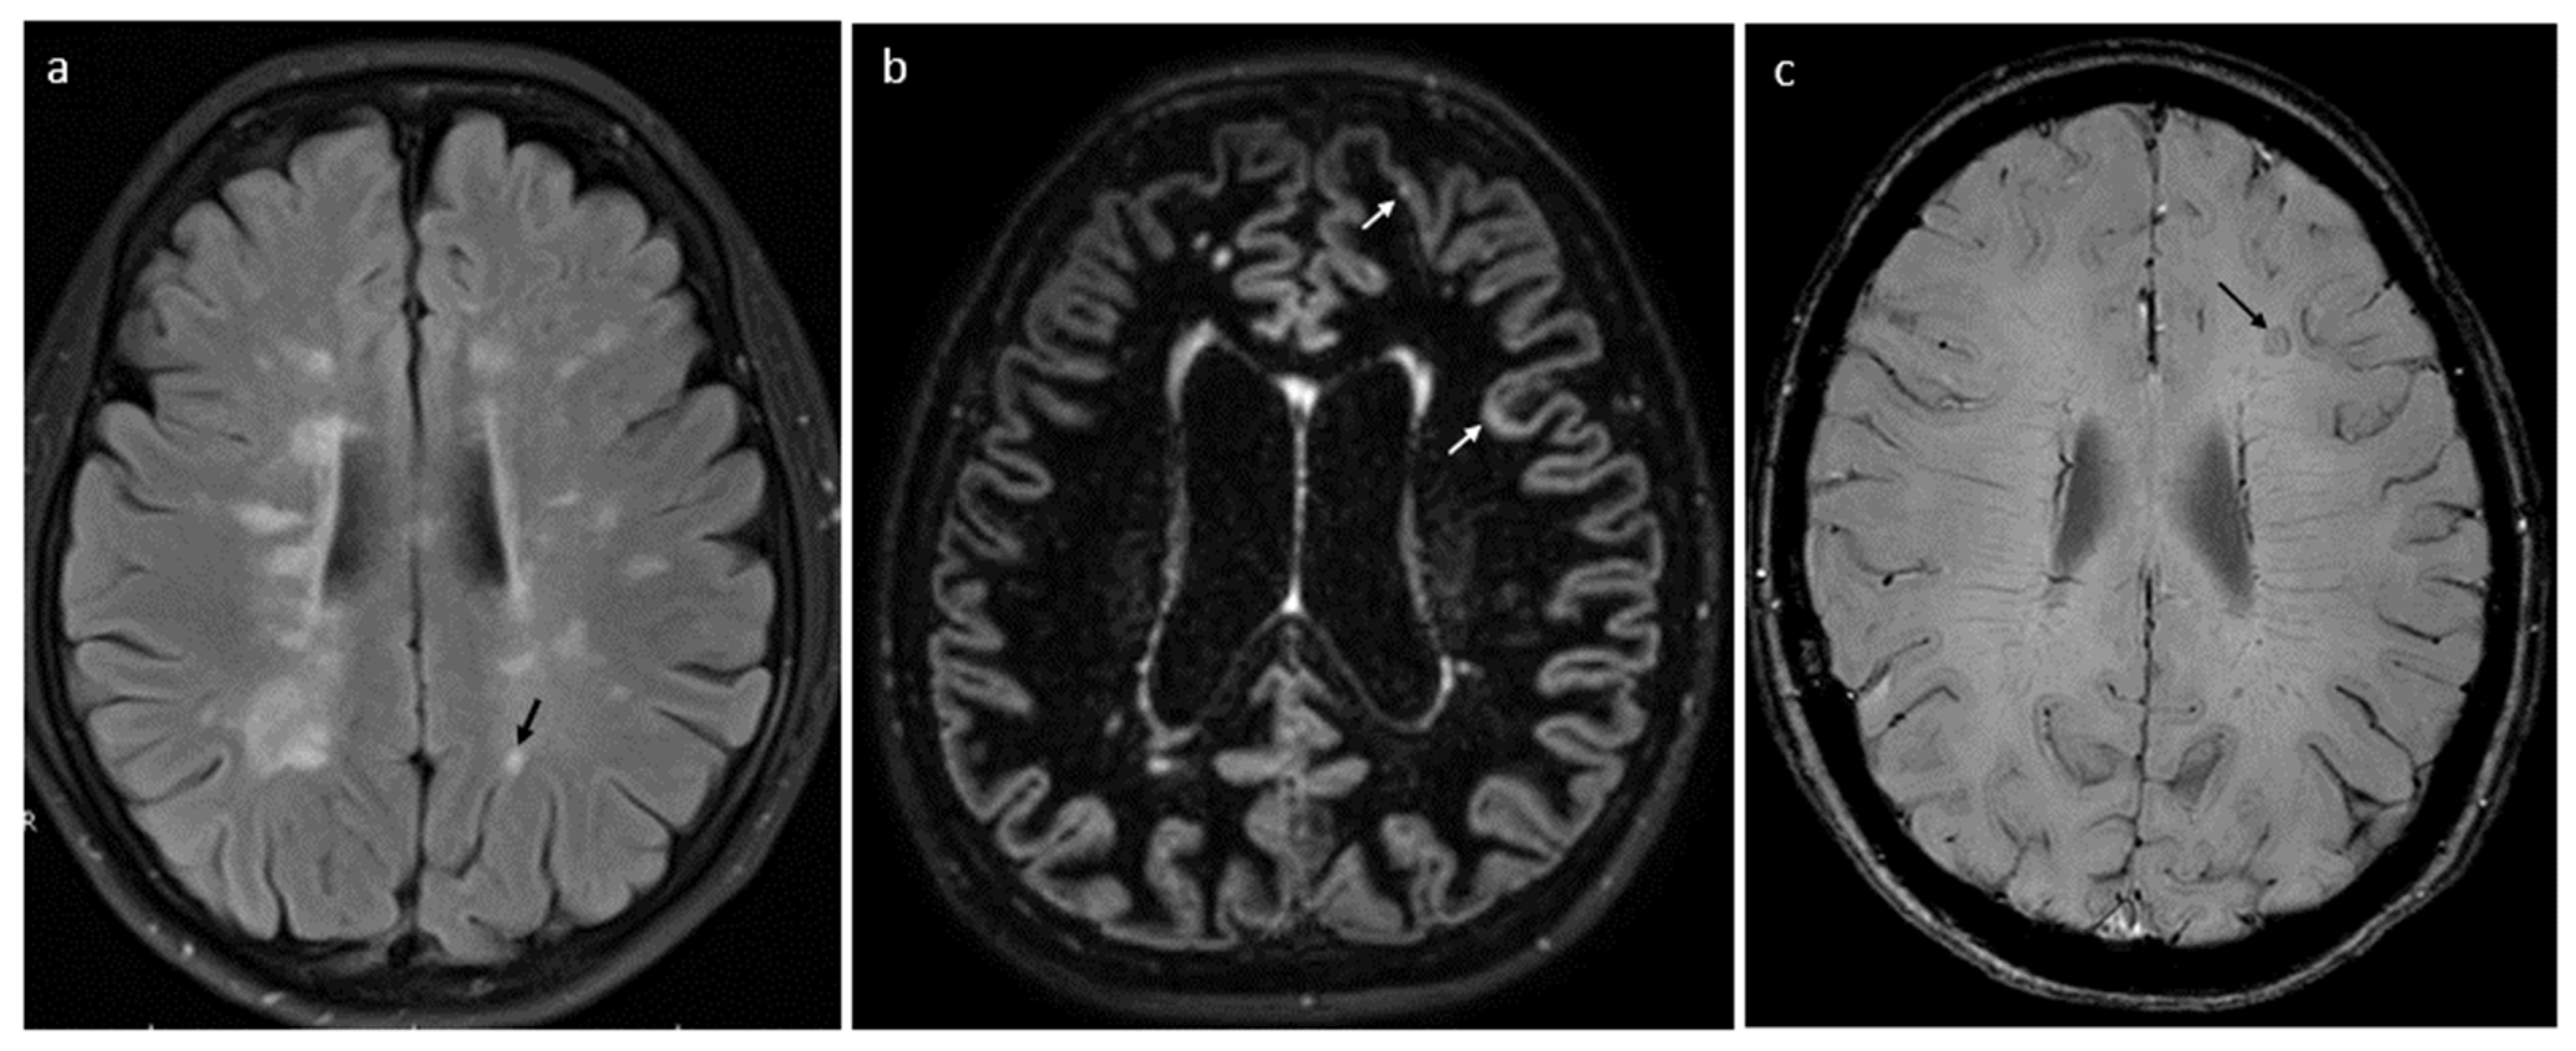

| Radiological (MRI) | SEL | constant and concentric volumetric expansion in T2, with concurrent reduction in T1-weighted sequence, revealed in subsequent 2–3 MRI scans | specific demyelinative lesions–sites of chronic inflammation | [96,97,98,99,100] |

| PRL | typical rim surrounding at least 75% of lesion, which reflects the layer of iron-laden microglia and macro-phages, accompanying demyelination and axonal transection (phase imaging, SWI or multi-gradient echo sequences) | specific demyelinative lesions—sites of chronic inflammation | [96,97,98,99,100] | |

| “dirty-appearing white matter” | ill-defined hyperintense areas, located mainly around the lateral ventricles | diffuse neuronal damage with chronic inflammation | [104,106] | |